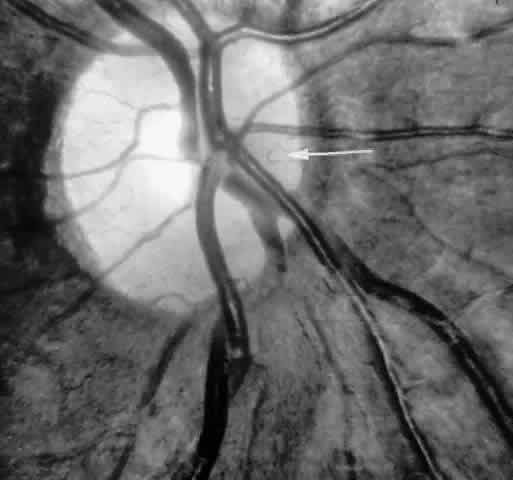

Occlusions of the central retinal artery and major arteriolar branches are probably most frequent in young patients with homozygous sickle cell anemia; however, they may also occur with other sickling genotypes (Fig. 7).39,83,84 They may cause permanent or transient visual loss and can occur simultaneously in both eyes.85–87 Arterial occlusion has also been reported to occur as a complication of retrobulbar anesthesia and following compression of the eye during photocoagulation (Fig. 8).88

Fig. 7. Transient perimacular arteriolar occlusions in a 32-year-old patient with SC disease, who presented with decreased vision in the right eye (20/40) after being tackled while playing football. A. Photograph of right macula showing a white, edematous retina and a cherry red spot due to multiple arteriolar occlusions. B. Fluorescein angiogram shows multiple avascular areas, particularly at the temporal raphe (arrowheads), and an irregular perifoveal capillary network (open arrows).

Fig. 8. A 27-year-old woman with homozygous sickle cell anemia and stage III sickle cell retinopathy. A. Three days after scatter photocoagulation to the right eye, a photograph of the right eye shows retinal arteriolar occlusions causing a white, edematous macula, a cherry red spot, and a cotton-wool spot superior to the macula. B. Fluorescein angiogram clearly shows the occluded arteriole superiorly, but no occlusion in the perifoveal or temporal macula. C. However, a fluorescein angiogram taken 1 year later demonstrates an irregular perifoveal capillary network with areas of capillary nonperfusion (arrows). D. Of interest, the left eye simultaneously developed an area of capillary nonperfusion, demonstrated by a cotton-wool spot nasal to the fovea. E. Two years later, there is resolution of the cotton-wool spot in the left eye, but a retinal depression sign remains, as demonstrated by an abnormal light reflex in the area nasal to the fovea (arrows).